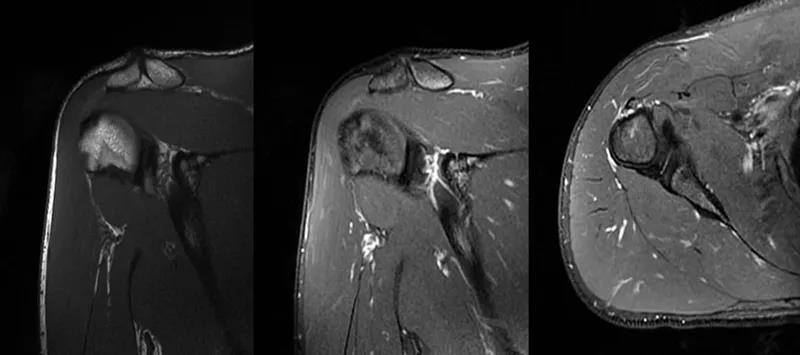

2、MRI检查MRI目前是诊断肩袖疾病中最常用的检查,可以直观的观察肩袖肌腱。

图24 a.肩袖全层撕裂;b.正常MRI

图25 巨大肩袖损伤(冈上肌)